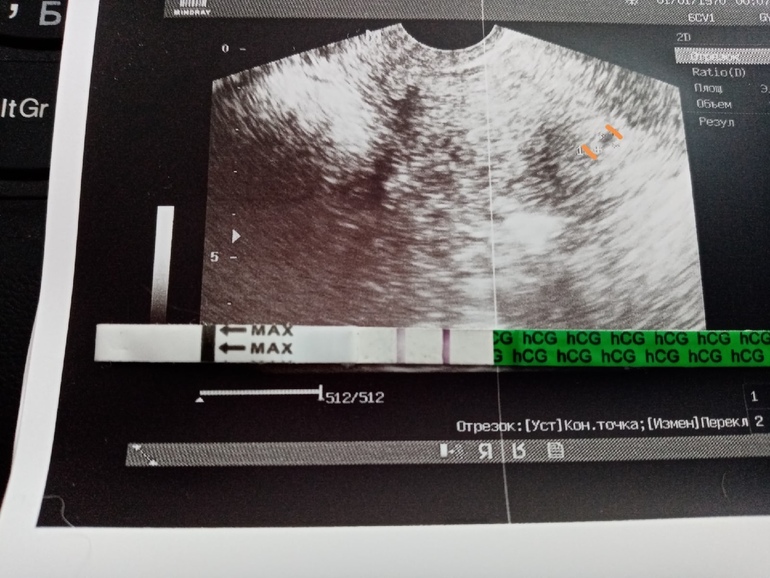

21.08.2020 - УЗИ показало маленькую бусинку в полости матки, врач сказала, что соответствует она примерно сроку 3\4 недели, сердечных сокращений пока нет.

22.08.2020 - ХГЧ 2159, что соответствует срокам по УЗИ.